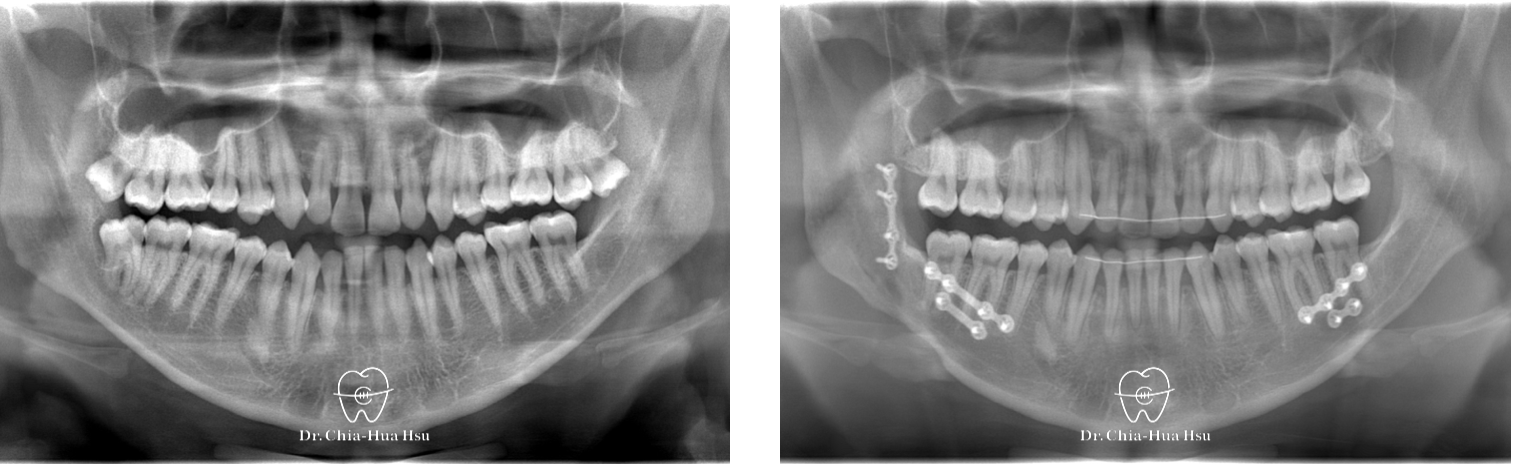

手術前使用軟體模擬骨塊移動路徑,以方便手術中定位。

治療前

治療後